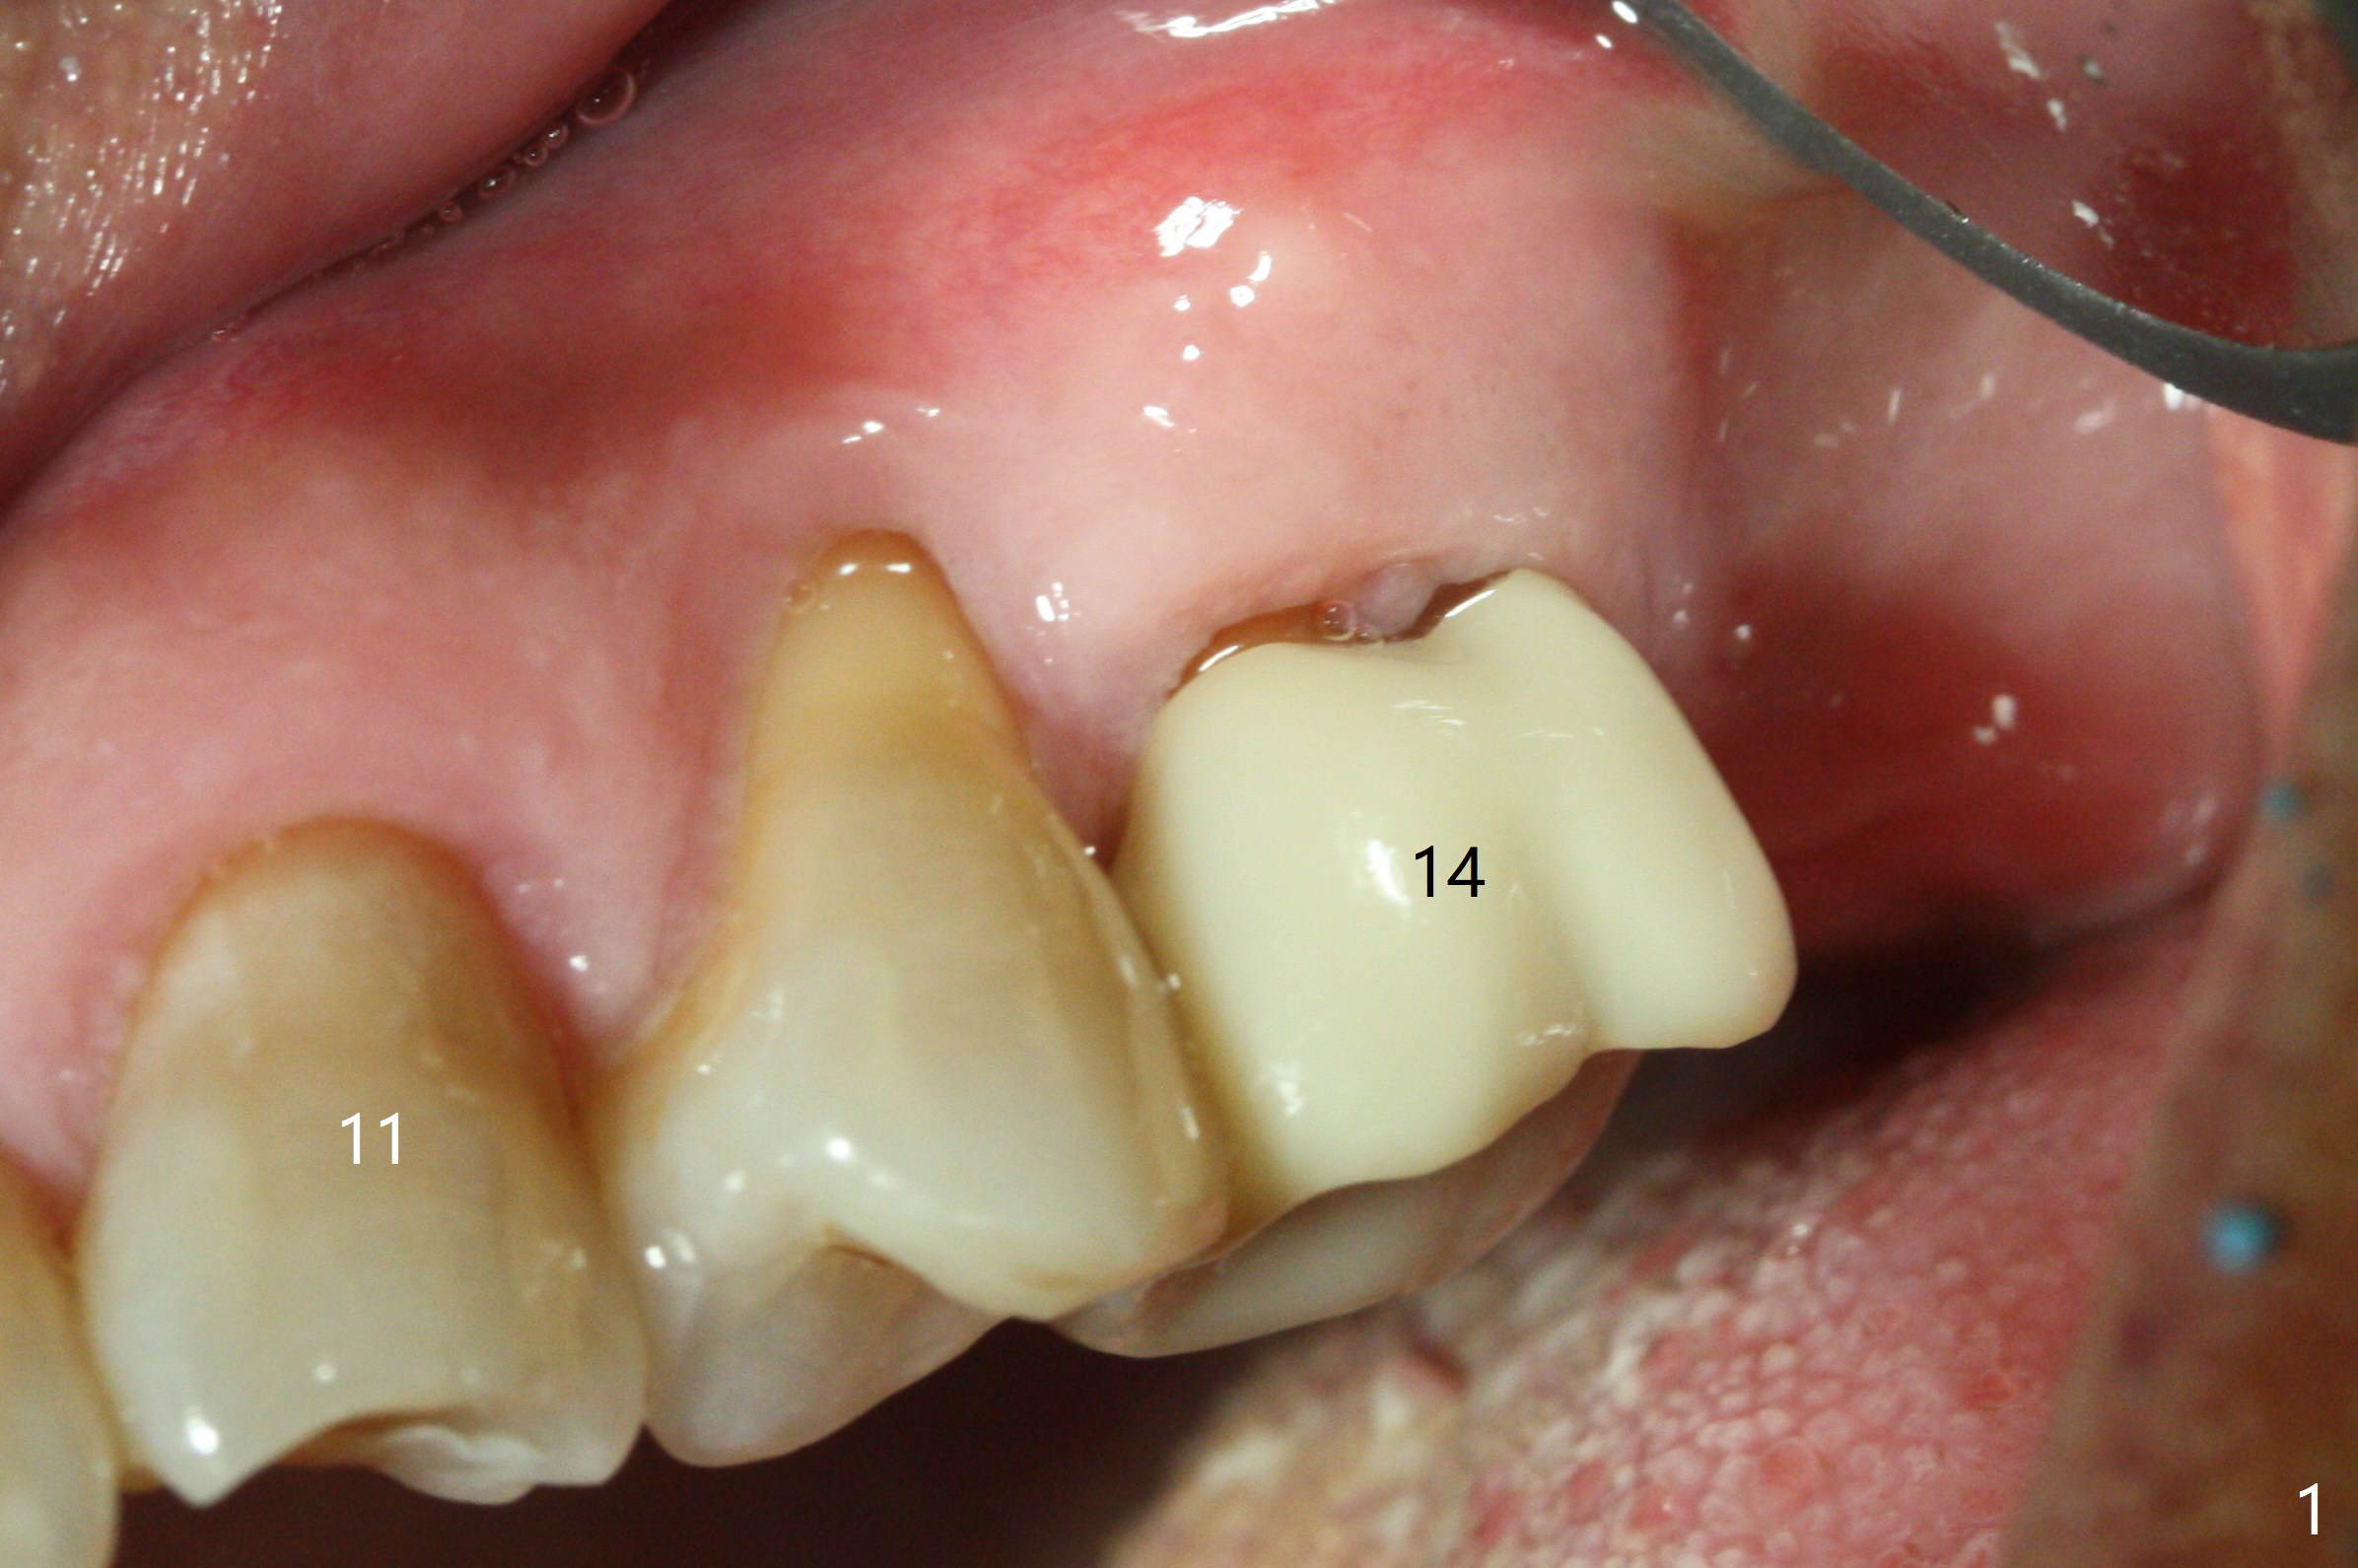

After extraction of the tooth #14 (Fig.1) and removal of granulation tissue associated with a distal fistula, a 1.6 mm drill is used to initiate osteotomy in the septum for 9 mm, followed by insertion of a 7 mm long parallel pin (Fig.2).  The length of the subsequential osteotomy is 11 mm until 4.8 mm in diameter (overprep as will be shown below).  The bone is hard so that sinus lift fails with 4.8 mm Magic Expander.  Since a 5x9 mm dummy implant is placed with stability, a definitive implant with the same dimension is chosen with >50 Ncm (Fig.3,4).  Prior to and after abutment placement, Vera graft is placed (*).  The provisional perforates with loose abutment 3.5 months postop.  A 6x4 mm healing abutment is placed.  Osteointegration occurs 4 months postop (Fig.5,6).